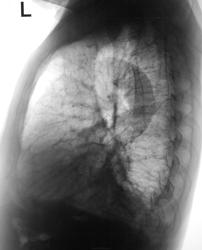

Пол пациента: Мужской пол Тип патологии: Воспалительное заболевание неинфекционной природы Область исследования: Грудная клетка и верхние дыхательные пути Методы исследования: Rg Направлен с диагнозом левосторонней пневмонии https://radiomed.ru/sites/default/files/styles/case_slider_image/public/user/12/2.dscn1726.jpg?itok=GltTbd_R https://radiomed.ru/sites/default/files/styles/case_slider_image/public/user/12/3.dscn1726a.jpg?itok=nynxxYyl ID:30074 Wed, 24/07/2013 - 18:15 #1 Сергей Кузьминов Offline Last seen: 1 year 3 months ago Joined: 06.10.2012 - 15:51 Posts: 11813 Слева жидкость в заднем синусе, в прикорневых зонах-непорядок.особенно справа.Средостение ненормально,может его порезать? Wed, 24/07/2013 - 20:32 #2 медсанчасть рег... Offline Last seen: 11 years 3 months ago Joined: 11.06.2013 - 10:46 Posts: 136 ПО прямой жидкость, по боковой S8-9. опять дифф.ряд.Да и сердце расширено. Wed, 24/07/2013 - 20:57 #3 Катенёв Валенти... Offline Last seen: 7 years 3 months ago Joined: 22.03.2008 - 22:15 Posts: 54876 медсанчасть регион 12 wrote: опять дифф.ряд. Интересно, какой дифряд выплывает? Wed, 24/07/2013 - 21:09 #4 maker4ik Offline Last seen: 8 years 9 months ago Joined: 19.10.2011 - 17:49 Posts: 2682 Пневмония в 9 с выпотом. 2 недели лечим, дальше в зависимости от контроля. Wed, 24/07/2013 - 21:31 #5 dim--lit Offline Last seen: 9 years 2 months ago Joined: 02.10.2010 - 17:25 Posts: 32 Абсолютно согласен с пневмонией в S9, S8, осложненной плевральным выпотом!Только вот контроль можно сделать через неделю) Wed, 24/07/2013 - 21:48 #6 медсанчасть рег... Offline Last seen: 11 years 3 months ago Joined: 11.06.2013 - 10:46 Posts: 136 Начнем с клиники,уточнимся Т-гр.на н\долевой бронх,уточнимся по сердцу. Wed, 24/07/2013 - 21:49 #7 Катенёв Валенти... Offline Last seen: 7 years 3 months ago Joined: 22.03.2008 - 22:15 Posts: 54876 Клиника пневмонии (со слов лечащего врача) Wed, 24/07/2013 - 22:14 #8 медсанчасть рег... Offline Last seen: 11 years 3 months ago Joined: 11.06.2013 - 10:46 Posts: 136 А Т-гр. Wed, 24/07/2013 - 22:23 #9 Катенёв Валенти... Offline Last seen: 7 years 3 months ago Joined: 22.03.2008 - 22:15 Posts: 54876 Томограмм не делали. Wed, 24/07/2013 - 22:38 #10 Дмитрий Волегов Offline Last seen: 3 years 9 months ago Joined: 22.05.2013 - 00:32 Posts: 1148 Справа купол диафрагмы нечеткий, и что-то там мерещится.Приложения: С Уважением, Дмитрий. Thu, 25/07/2013 - 15:51 #11 Катенёв Валенти... Offline Last seen: 7 years 3 months ago Joined: 22.03.2008 - 22:15 Posts: 54876 Дмитрий Волегов wrote: Справа купол диафрагмы нечеткий, и что-то там мерещится. Контроль будет обязательно

Слева жидкость в заднем синусе, в прикорневых зонах-непорядок.особенно справа.Средостение ненормально,может его порезать?

ПО прямой жидкость, по боковой S8-9. опять дифф.ряд.Да и сердце расширено.

Пневмония в 9 с выпотом. 2 недели лечим, дальше в зависимости от контроля.

Абсолютно согласен с пневмонией в S9, S8, осложненной плевральным выпотом!Только вот контроль можно сделать через неделю)

Справа купол диафрагмы нечеткий, и что-то там мерещится.